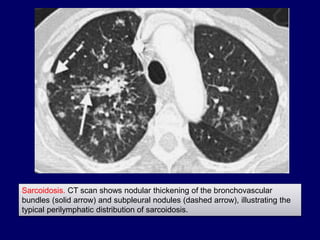

Sarcoidosis. CT scan shows nodular thickening of the bronchovascular

bundles (solid arrow) and subpleural nodules (dashed arrow), illustrating the

typical perilymphatic distribution of sarcoidosis.

Sarcoidosis. CT scanshows nodular thickening of the bronchovascular bundles (solid arrow) and subpleural nodules (dashed arrow), illustrating the typical perilymphatic distribution of sarcoidosis.